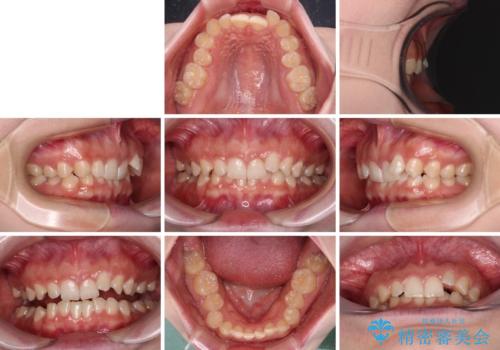

- 前歯のデコボコとディープバイトを気にして来院された患者様です。

左上前歯前方に飛び出しているため、歯列全体が前方に移動している状態でした。

左上の歯列は補助装置により速やかに移動し、1年程度で奥歯の咬み合わせが改善され、1年3ヶ月の短期間でしっかりと仕上げることができました。